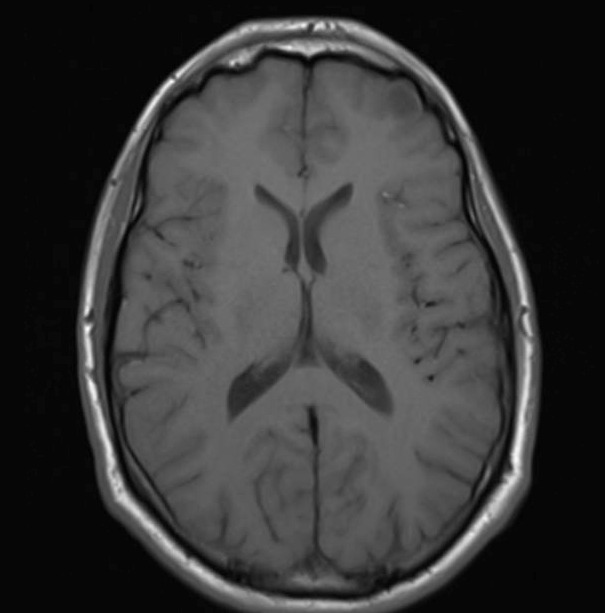

Figure 4: Samples from the non-tumorous class across different imaging planes. The top row shows healthy brain scans without visible abnormalities, and the bottom row shows examples of non-tumorous lesions (e.g., cysts or abscesses).

Non-tumorous: This control class includes both healthy brain scans without visible abnormalities and scans with non-neoplastic, space-occupying lesions (e.g., cysts, abscesses, or vascular malformations). Incorporating such cases improves the dataset’s robustness for both binary (tumorous vs. non-tumorous) and multi-class classification tasks. Figure 4 presents representative examples of healthy and non-tumorous lesion cases across different imaging planes.